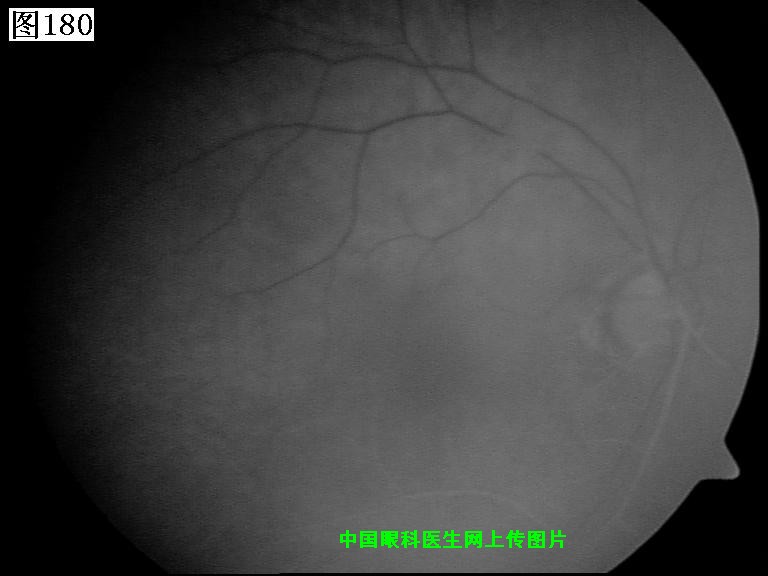

177 178 179 180